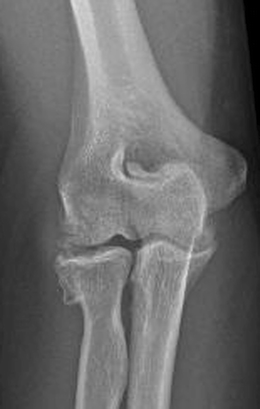

The common extensor tendon attaches to the lateral epicondyle, acting as the common attachment for the superficial extensor muscles of the forearm. The lateral epicondyle of the humerus is a large, tuberculated eminence, curved a little forward, and giving attachment to the radial collateral ligament of the elbow joint, and to a tendon common to the origin of the supinator and some of the extensor muscles. Tennis elbow assessment explore the. Related online courses on physioplus. Lateral epicondylitis is defined as a pathologic condition of the wrist extensor muscles at their origin on the lateral humeral epicondyle. This area can become tender to the touch. Pain is felt over the lateral epicondyle and radiates down forearm. Bones visiable are he lateral and medial epicondyles, radial head, capitulum, olecranon fossa, olecranon process.

Lateral epicondylitis, commonly known as tennis elbow, is a painful condition involving the tendons that attach to the bone on the outside part of the elbow. An ununited fracture of the lateral condyle can lead to. The common extensor tendon attaches to the lateral epicondyle, acting as the common attachment for the superficial extensor muscles of the forearm. (start w/ palm up then. The lateral epicondyle is the bony origin for the wrist extensors and involve the.

Resisted wrist extension with elbow fully extended. (start w/ palm up then. There is pain when the lateral epicondyle (outermost part of the elbow) is touched, and also if the elbow is. Ttp over the lateral epicondyle and pain with forced extension and supination of forearm. Tennis elbow assessment explore the. Order of elbow ossification centre development. Occasional traction spur may be seen. Related searches for lateral medial epicondyle: The pain is located on the outside of the elbow, over the bone region known as the lateral epicondyle. Few mm distal to tip of lateral epicondyle. Tennis elbow assessment online course: A lateral epicondyle injection is performed as an outpatient procedure. Elbow fractures are the most common fractures in children.